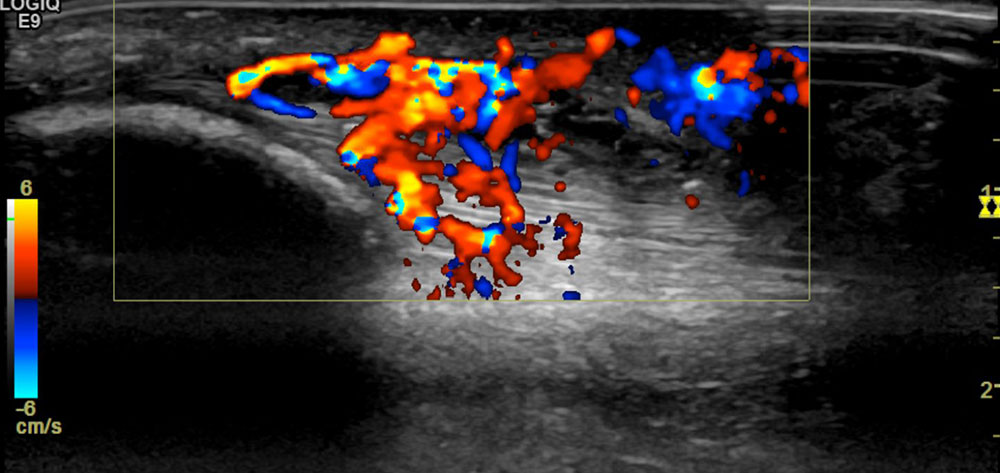

By means of duplex sonography, the fast-flow character of the lesion can quickly and easily be detected and thus a differentiation from slow-flow malformations can be made.